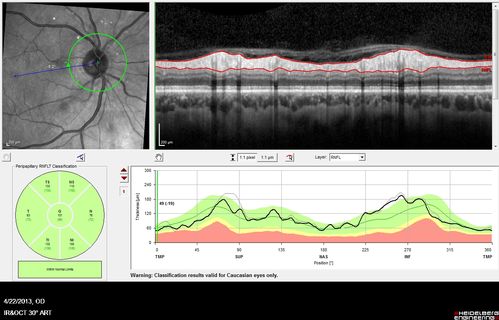

Malignant Hypertension - Cotton Wool Spots - Elschnig Spots - Optic Nerve Edema (NFL Scan - Black Line this visit, Gray line 6 weeks ago)

Nerve Swelling is Less